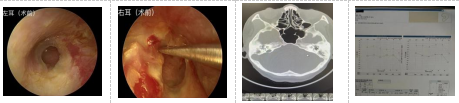

患者王某,女,54岁,因“反复双耳流脓伴听力下降10余年”自行佩戴助听器入院,入院诊断双侧慢性中耳炎,术前听力提示双侧传导性聋,气骨导差约40dB。为确保手术成功开展,我院耳鼻喉科团队对患者的病情进行了全面评估,完善相关专业检查,为患者制定了一套完善的手术治疗方案。双耳分两次行耳内镜下鼓室成形术+人工听骨链重建术,手术顺利,术后1月复查双耳鼓膜完整,听力图提示气骨导差约15dB-20dB,患者听力明显改善,已摘除助听器。

术前

术中置入人工听骨PORP